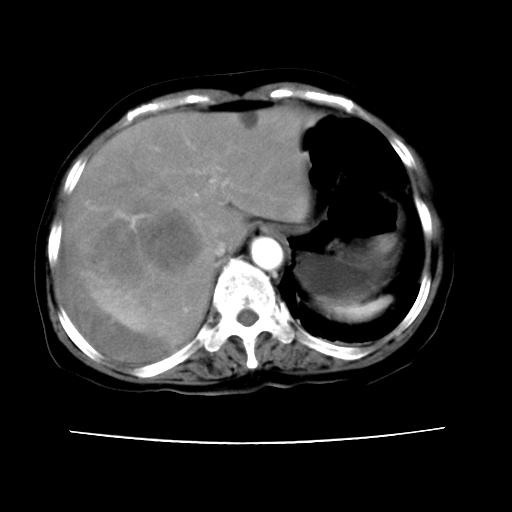

2008-11-10ct平扫(其间去中山医院诊治未行特殊治疗)

2008-11-10ct平扫见并肝内、血膜下血肿基本吸收,肝内低密度灶缩小。此时再做增强ct应有显着意义。对患者/医者都好!

从平扫+增强及治疗后复查片,病变明显缩小,不考虑肝癌出血可能,还是考虑为良性病变可能性大;单纯血肿并包膜下积液吧,病变强化没法解释,肝血管破裂出血吧,增强不符合典型血管瘤的表现,良性肿瘤破裂出血吧,复查片看来好像也不太支持(没做强化也不太好说)。本人还是考虑单纯肝内血肿并包膜下积液,强化是不是血管有外渗。

患者自6月至11月,如果是肝癌,没有经过特殊治疗,想必应该会有所进展吧,而不是ct所见,反而似有病灶减小的趋势。建议增强。